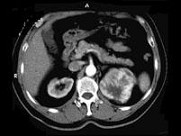

- 多项选择题男性,65岁。左侧腰背部胀痛伴无痛性全程血尿3个月余, CT平扫及增强检查如图所示,下列说法正确的是

A、平扫时见左肾上极有一软组织肿块影,其边界较清楚

B、增强扫描肾皮质期可见肿块明显强化,其内亦有无强化区

C、增强扫描肾实质期可见肿块强化迅速下降,但密度比平扫时仍要高

D、考虑为左侧肾癌

E、考虑为左侧肾错构瘤